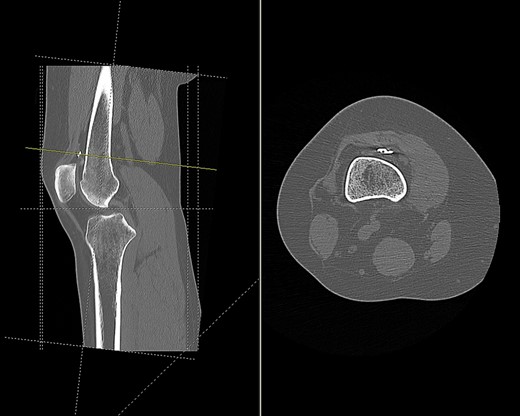

CT (Fig. 1) and MR imaging showed an endobutton and endocord sitting superior to the patella, with both impinging upon the articular surface of the medial patella facet. A metal susceptibility artefact was seen at the medial femoral condyle, which was identified as an interference screw.

CT scan of the right knee showing the endobutton in suprapatellar pouch (sagittal and axial view).

Imaging enabled assessment of the graft tunnels (Figs 2 and 3). It appeared that an oblique tunnel had been drilled from the medial epicondyle to the anterior cortex of the femur at the level of the suprapatellar fat pad.

CT scan of the right knee showing entry point and oblique path of femoral tunnel at medial epicondyle (sagittal and axial view).

CT scan of the right knee showing perforation of anterior femoral cortex (sagittal and axial view).

Based on tunnel positions, we conclude that the original surgeon had perforated the anterior femoral cortex when drilling from the medial femoral condyle. Due to this an anterior cortex endobutton fixation was used to supplement the medial condylar interference screw fixation. A degree of likely soft tissue interposition in the suprapatellar region led to migration of the endobutton, and subsequent rupture from its scar tissue bed following minimal trauma.